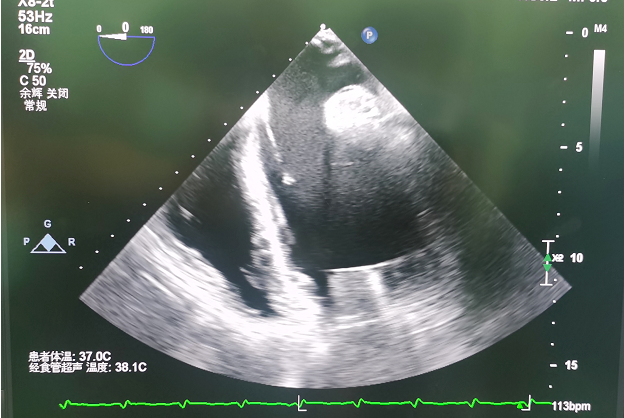

▲人工心脏血泵入口正对二尖瓣

心室腔内的血液可以顺畅进入血泵